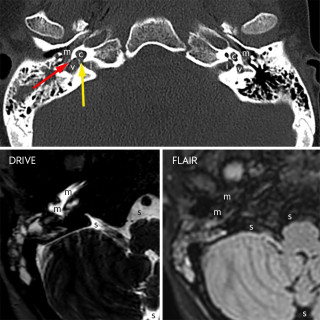

CT-bildene er fra en undersøkelse med opptak uten intravenøs kontrast. Bildet til venstre viser høy attenuasjon i myokard i venstre ventrikkel, og i mindre grad i høyre ventrikkel. Attenuasjonen er tilnærmet lik skjelett i bildet, og tettheten kan passe med forkalkninger. Opptaket er gjort på en spektral-CT, som har økt mulighet for å differensiere mellom ulike vevstyper. Maskinen utnytter de ulike energinivåene i røntgenstrålen, og den kan skille mellom grunnstoffer som jod og kalk utfra absorpsjonsnivået, da begge gir høy attenuasjon. Kalksuppresjon, vist på bildet til høyre (B), bekrefter...